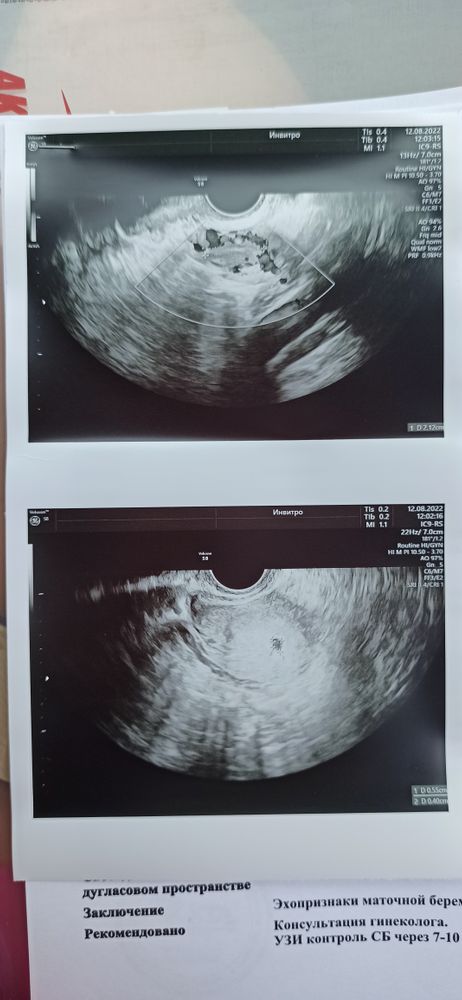

Всем привет, сегодня прошла первое УЗИ. Фото прикрепляю )

Срок 5 недель 3 дня, эмбриональные поменьше. Показатели в норме, через 2 недели слушать сердечко ❤️